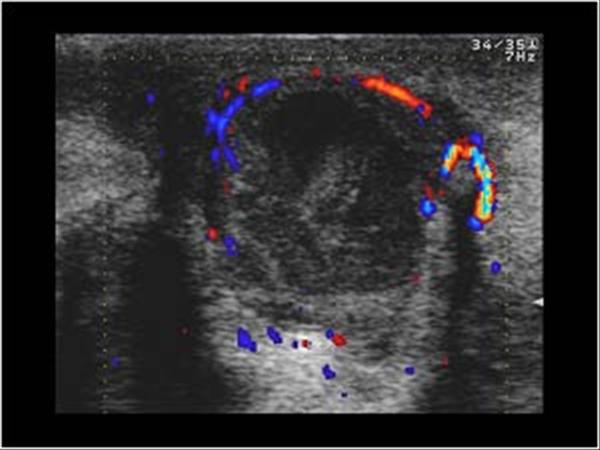

Apxe vú

Apxe vú - Ảnh 4

» Thông tin: Nữ giới – 21 tuổi.

» Lâm sàng: Sưng đau tuyến vú.